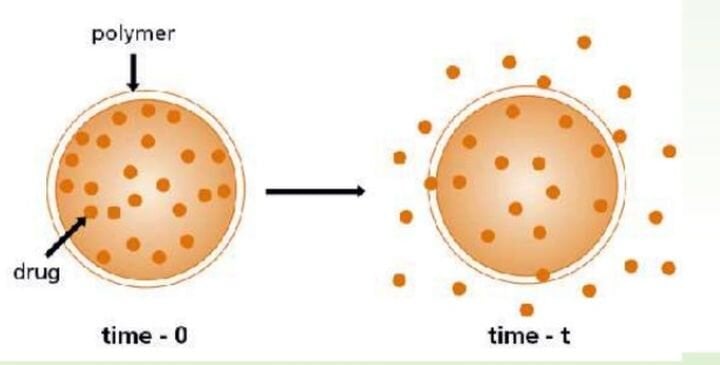

Polymers Are Used in Medicinal Tablets: A 3D Printing Opportunity

EOS and Merck Group’s partnership to develop 3D printed medicinal tablets may actually be a lot more interesting than initially thought.

EOS Getting Into Medical Tablet Business With Merck

EOS is going into business with Merck Group to develop a way to 3D print medicine in tablet form, but they will have some challenges.